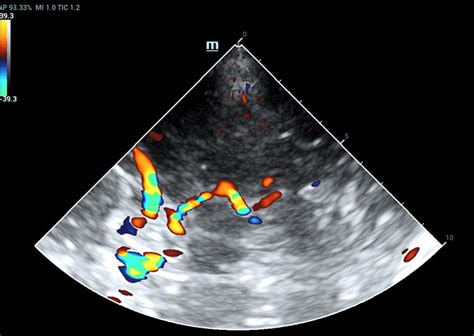

Nėštumo trukmė paprastai skaičiuojama nuo paskutinių mėnesinių pirmos dienos, net jei pastojimas įvyko vėliau. Tai yra standartinis akušerinis metodas, pagal kurį apskaičiuojama nėštumo savaitė. Tiksliai nustatyti nėštumo amžių padeda ultragarsinis tyrimas - ypač pirmąjį trimestrą, kai vaisiaus dydis yra vienas iš patikimiausių rodiklių.